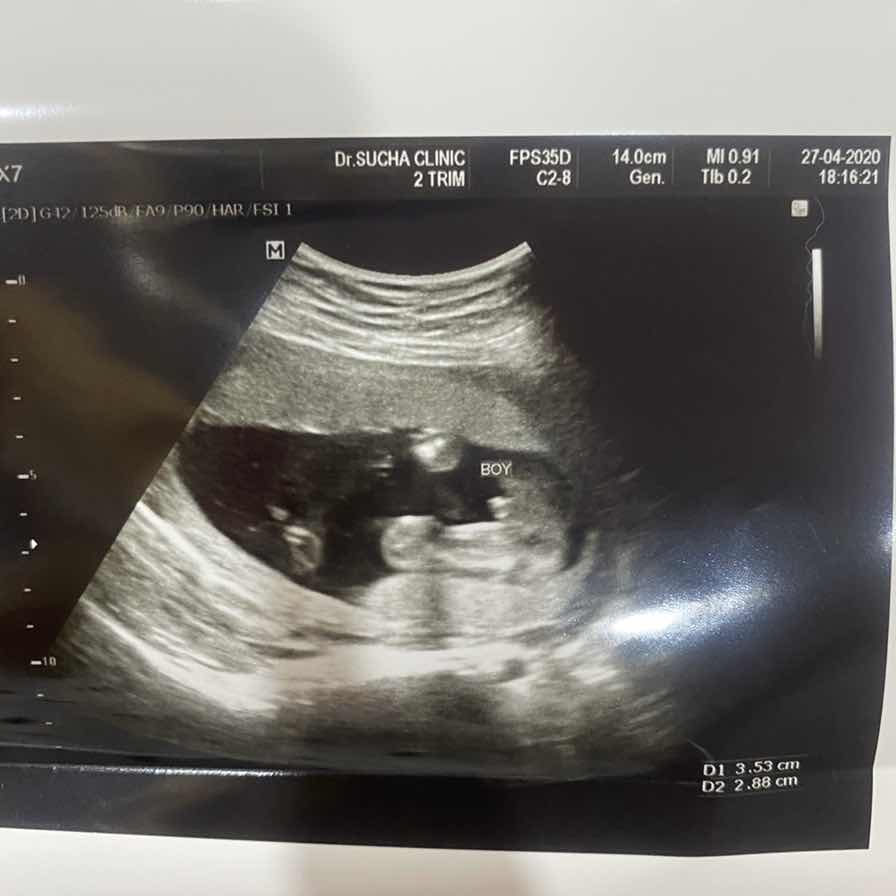

ชายค่ะ

ชายคับ